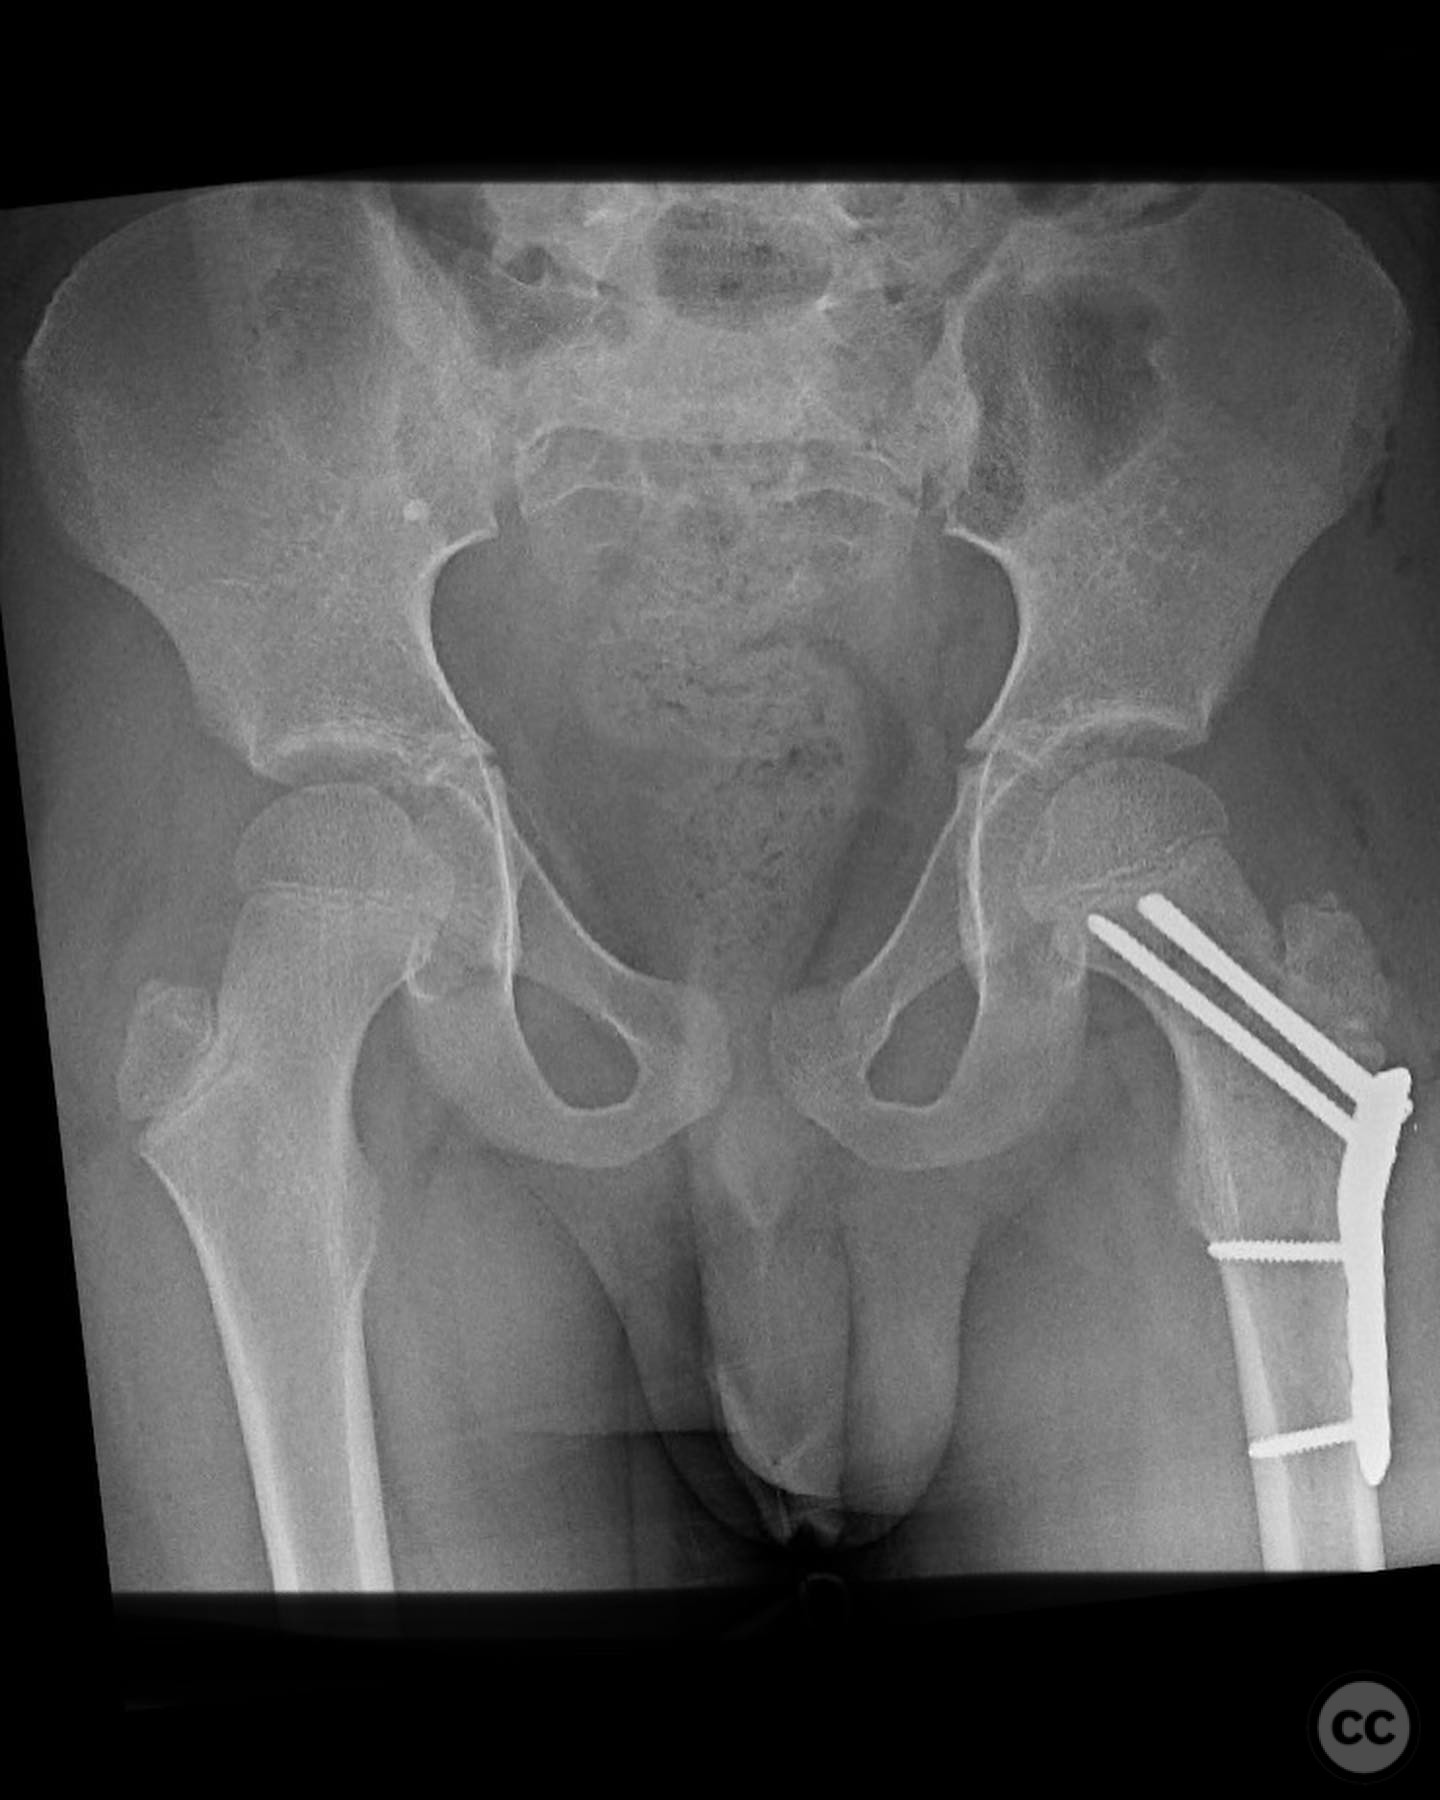

Displaced Pediatric Femoral Neck Fracture in an 8-Year-Old Boy

Clinical and radiological findings:  An 8-year-old boy fell approximately 15 feet from a treehouse, sustaining a displaced femoral neck fracture. There were no associated injuries to the head, spine, chest, or abdomen. The initial radiological assessment confirmed a displaced fracture of the femoral neck. Neurovascular examination was unremarkable.

Planning remarks:  The preoperative plan involved achieving a direct anatomic reduction and stable fixation of the femoral neck fracture. The surgical approach considered was a modified Smith-Petersen approach for optimal visualization and reduction, followed by a separate lateral approach for implant application.

Anatomical surgical approach:  A modified Smith-Petersen approach was utilized, involving an incision along the anterior aspect of the hip, allowing for direct visualization of the femoral neck. Subperiosteal dissection was performed to expose the fracture site without compromising the surrounding musculature. A separate lateral approach was employed for the application of fixation devices.

The surgeon emphasized the importance of achieving a high-quality reduction and stable fixation due to the displacement pattern of the fracture. A meticulous surgical approach was critical to avoid malreduction, which is not well-tolerated in pediatric patients. The modified Smith-Petersen approach provided excellent visualization for anatomic reduction, minimizing soft tissue damage.

Orthopaedic implants used:   Angle stable static device (specific brand not mentioned).